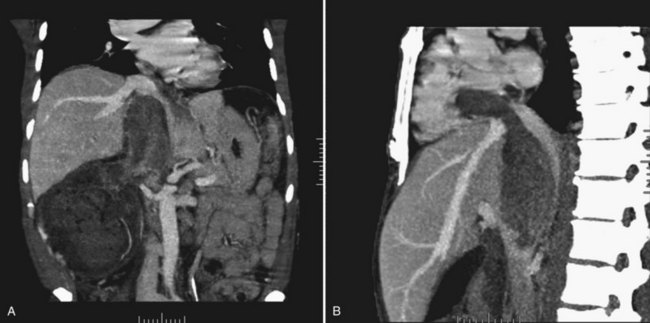

Tumor thrombus involving the IVC should be suspected in patients with lower extremity edema, varicocele, dilated superficial abdominal veins, proteinuria, pulmonary embolism, right atrial mass, or nonfunction of the involved kidney. MR venography is the authors’ preferred study for evaluating the presence and the distal extent of involvement of the IVC (Pritchett et al, 1987; Goldfarb et al, 1990) (Fig. 54–86). The use of invasive inferior vena cavography is limited to those patients with a nondiagnostic MR venogram or ultrasound evaluation, in those in whom MRI is contraindicated, and in patients who underwent preoperative angioinfarction with coils that would produce scatter leading to poor quality MR images (Fig. 54–87). Transesophageal echocardiography (Treiger et al, 1991; Glazer and Novick, 1997) and transabdominal Doppler ultrasonography (McGahan et al, 1993) are also useful. In patients with known IVC tumor thrombus the authors perform intraoperative transesophageal echocardiography to evaluate the distal extent of the tumor thrombus before making the incision.

Figure 54–86 A, Coronal MR image demonstrates tumor extending to the level of the diaphragm. B, Sagittal MR reconstruction demonstrates thrombus that extends farther into the right atrium. The patient would eventually require cardiopulmonary bypass and deep hypothermic circulatory arrest.

Figure 54–87 A and B, Preoperative cavogram demonstrating filling defect at the T10 level consistent with tumor thrombus in a patient with a large right renal mass. The patient required cardiopulmonary bypass and deep hypothermic circulatory arrest.